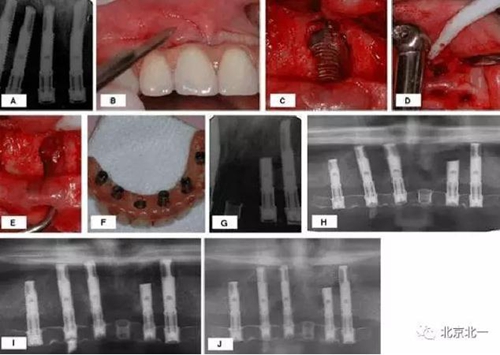

此外,也有学者应用冻干骨和胶原膜也成功修复了骨缺损。但是 Balshi 等学者认为相比引导骨再生,手术切除感染种植体的根尖区是更好的治疗方法。他们的治疗程序如图 2:

图 2 :

(A)种植体植入后即刻负载三月后的根尖周 x 线片;

(B–E)移除 21,切除 23 根尖 ;

(F)术后调整和修复;

(G) 术后口内 x 线片;

(H–J)种植体根尖切除后 2

(H)4

(I)6

(J)年的曲面断层